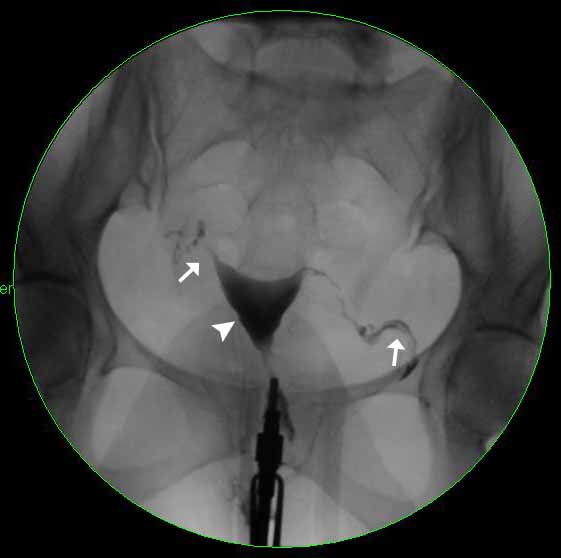

Image 3

Abnormal HSG showing obstructed left fallopian tube. The white arrowhead is pointing towards the uterus, which has filled with contrast and is normal in shape. The white arrow is pointing towards the right fallopian tube, which has begun to fill with contrast. Note that the left fallopian tube does not fill with contrast, indicating that it is obstructed.

Image 4

At a later point in time, this image shows contrast spilling from the right fallopian tube into the peritoneum (white arrow). Again, note that the left fallopian tube did not fill with contrast and that there is no spillage on the left side which indicates that the tube is obstructed and is not patent.